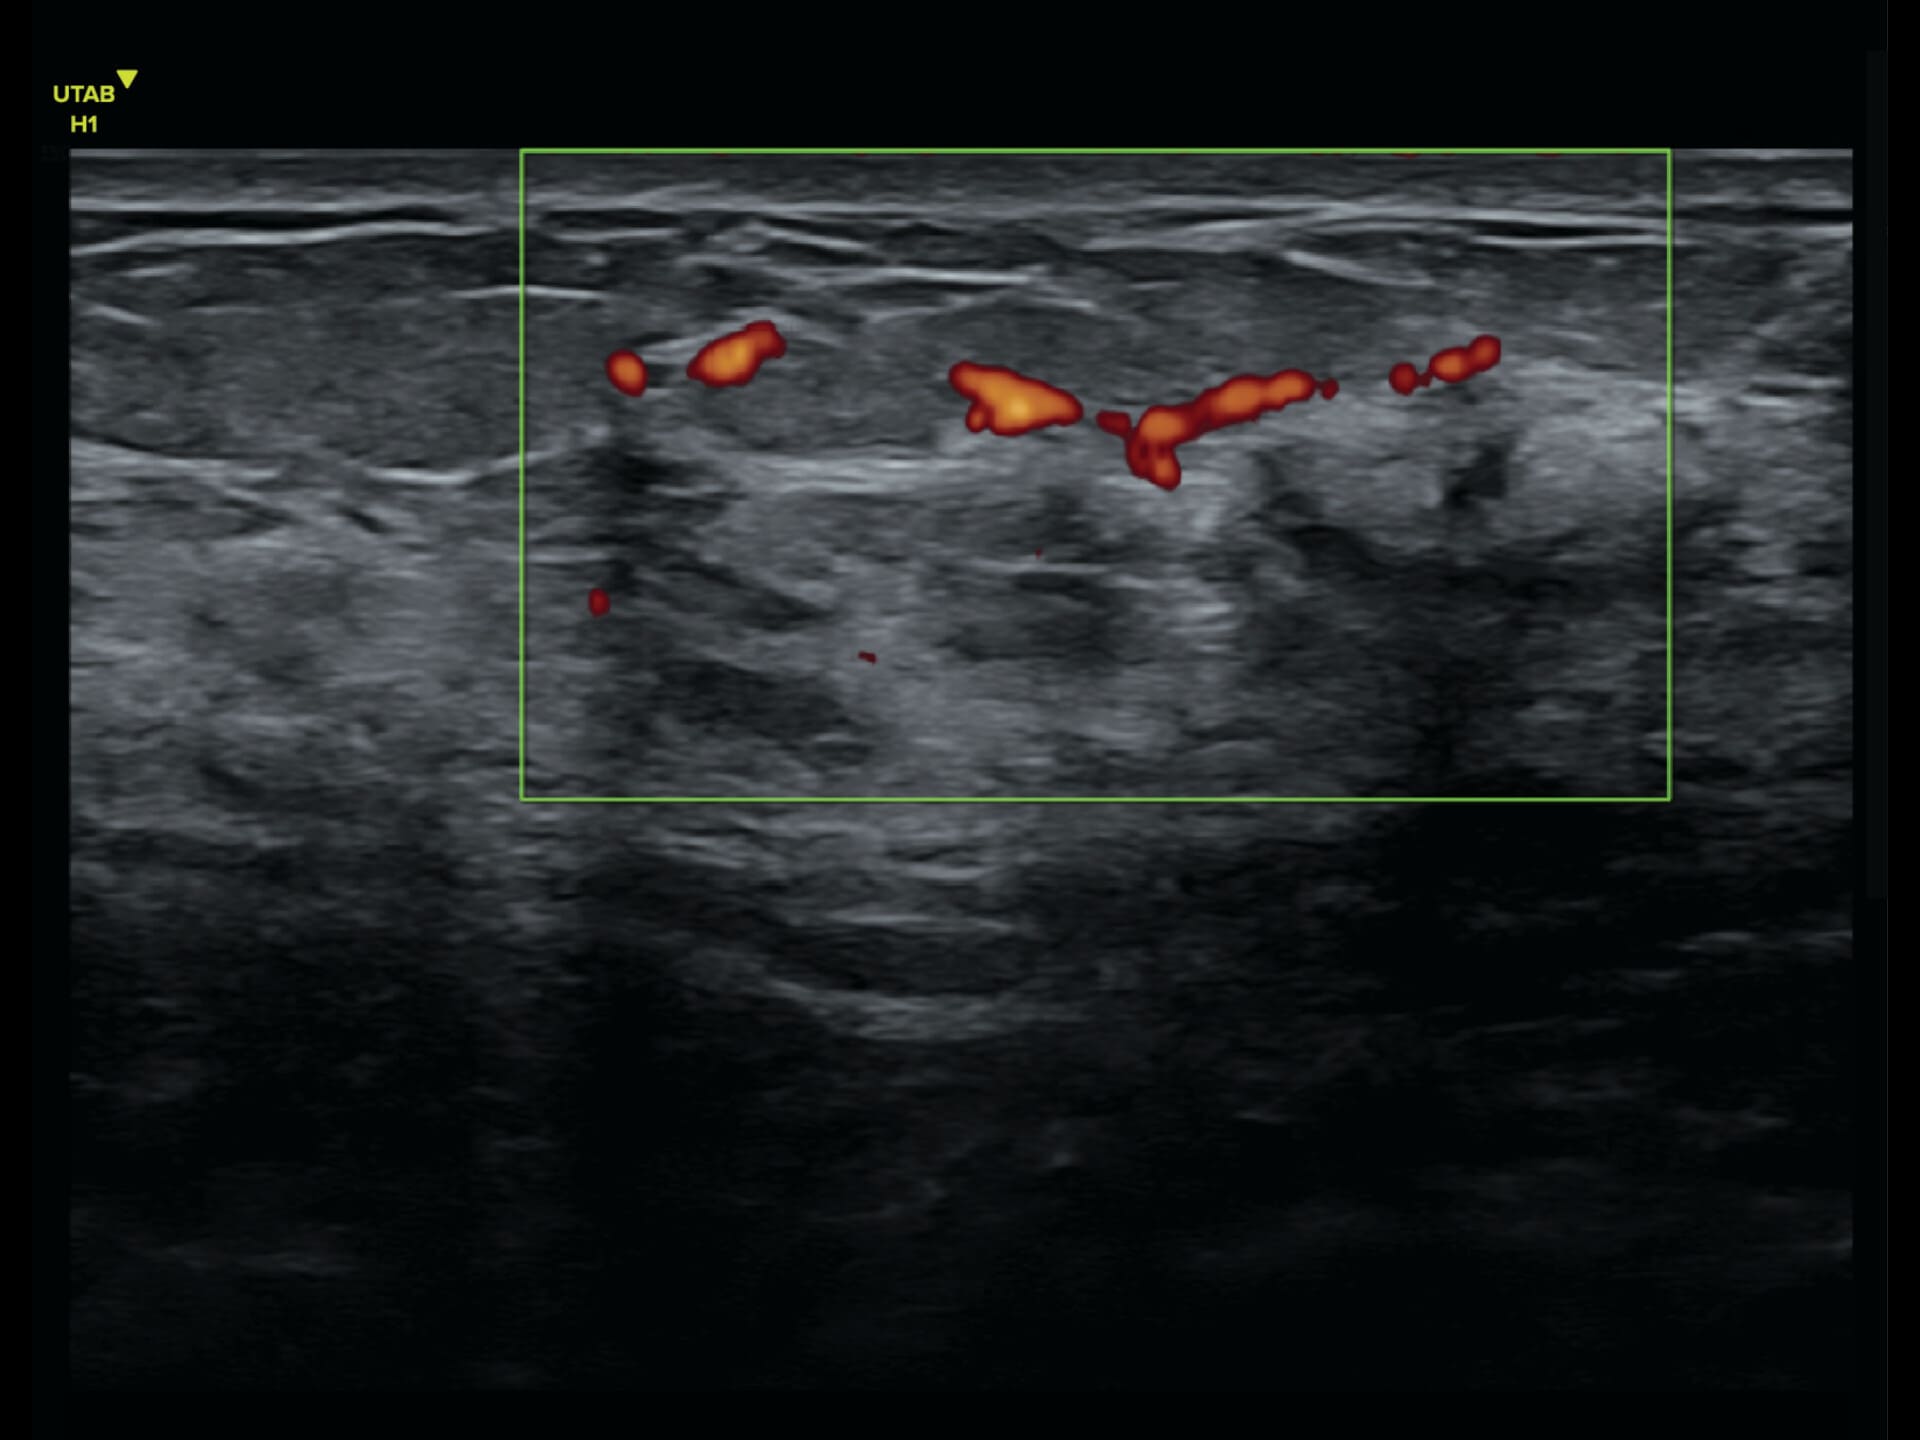

L9-2 Linear Array Probe

Crystal-clear imaging for muscles, vessels, and soft tissues—perfect for targeted exams and real-time procedures.

The L9 – 2 is a linear array ultrasound probe featuring advanced wideband technology, which enables a broader frequency range for superior image resolution and clarity. This enhanced imaging capability makes it ideal for a range of clinical applications.

The L9 – 2 is a linear array ultrasound probe featuring advanced wideband technology, which enables a broader frequency range for superior image resolution and clarity.

This enhanced imaging capability makes it ideal for a range of clinical applications.

Applications:

Musculoskeletal, Thyroid, Small Parts, Pediatrics, Peripheral Vascular, Breast, Obstetrics

B-mode, HI, XBeam, Speckle Reduction, Virtual Convex, M-mode, PW (Update, Duplex, Triplex, HPRF), CFM, PD